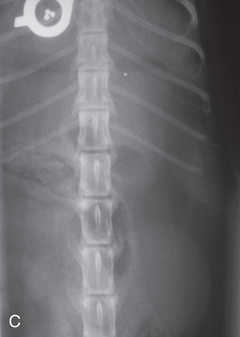

High-quality images are needed to see subtle changes in bone opacity, shape, and angulation of the vertebrae or vertebral column1,2 (Table 20.1). The common views of this portion of the axial skeleton are the lateral (L) and ventrodorsal (VD) views of the cervical, thoracic, thoracolumbar, lumbar, lumbosacral, sacral, and caudal vertebrae. Depending on the size of the patient, a full survey study is either four or five images of each orthogonal view.

MEASURE: Level of L1.

CENTRAL RAY: Level of L4 (palpate).

BORDERS: T12 to S1 (Just cranial to both the origin of the last rib and acetabulum).